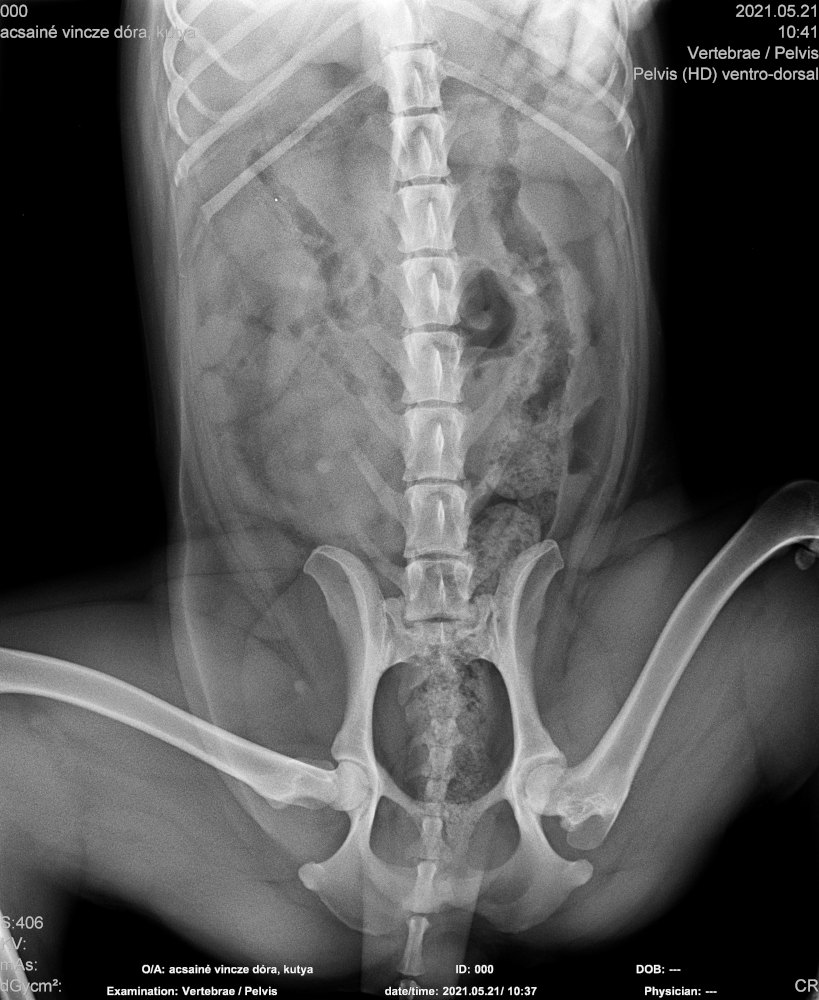

Füli kutyusunk egy jelenleg kb másfél éves, mentett, bántalmazott keverék, szuka kutyus (15 kg-os, vékony testalkatú, közepes magasságú, rövidszőrű keverék kutyus). Sérülése egy korábbi bántalmazásból eredt, mikor kiskutyaként husánggal úgy megverhették, hogy combnyaktörése lett. Ezt mi derítettük ki, mikor hozzánk került tavaly októberben. Akkor észrevettük, hogy aggasztóan sántít, és elvittük megröntgeneztetni. Több orvos véleményét is kikértem, és mindannyian azt tanácsolták, hogy műttessük meg (elég drasztikus műtéttel, a combcsontfej egy részét kivágták volna).

Molnár doktor úr egyedüliként, a röntgen kép alapján, arra bíztatott, hogy mivel a kutyus még növekedésének vége előtt állt, próbáljunk ki egy 3 hónapos csont- és porcépítő csomagot. Így is tettünk. Már kezdetben is nagy javulást észleltünk. Pár hét után el-elmaradozott a sántítás és szép lassan teljesen elmúlt. De természetesen nem elégedtünk meg ennyivel. Májusban az ivartalanítási műtét során kértem az orvost, hogy készítsen röntgenfelvételt Füli lábáról. A röntgen el is készült, és nagy örömünkre, már ez az állatorvos is azt mondta, hogy nincs szükség a combcsontfej műtétjére.